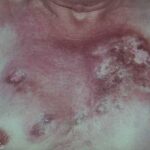

- Skin lesions are the most common manifestation of extrapulmonary disease. Cutaneous lesions favor exposed areas and enlarge over many weeks, from pimples that are minimally tender to well-circumscribed verrucous or ulcerative lesions, often with little inflammation. Verrucous lesions demonstrate raised irregular borders with crusting and purulent drainage, whereas ulcerative lesions are characterized by sharp and heaped-up borders with centrally located granulation tissue and exudate.